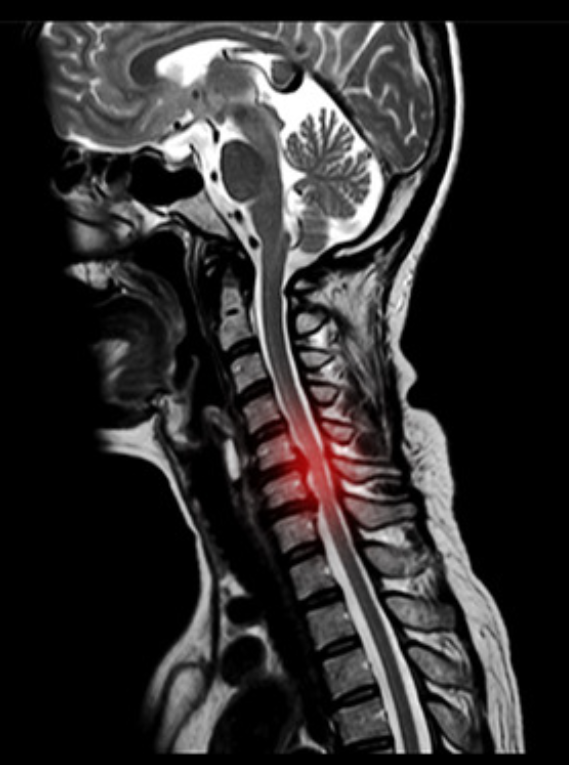

首のMRIで神経の圧迫所見がある場合確定診断します。

また頸椎MRIで脊髄の圧迫と信号変化があると頚髄症を強く考えます。

しかし、腕のしびれ痛みがかなり強い場合、腕や手の力が入らない場合、手の使いにくさが強い場合(お箸やボタンかけができなくなることがあります)、歩行が不安定であったり、よろけたりする場合は神経の圧迫がかなり強いことが考えられます。そのような場合はMRIを確認後、早期に手術ができる病院へ紹介することがあります。